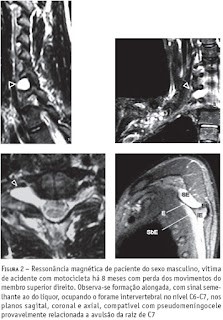

As meningoceles traumáticas ou pseudomeningoceles aparecem como massas extra-aracnóides com intensidade de sinal semelhante ao liquor, projetando-se para fora do canal medular e podem estar relacionadas à avulsão das raízes correspondentes. Essas alterações podem ser bem caracterizadas nas imagens axiais, coronais e sagitais.